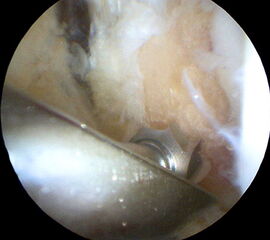

Nachfolgend wird die OP-Technik an einem rechten Sprunggelenk unter Verwendung von PEEK-Ankern veranschaulicht.

-

Abbildung 4 -

Abbildung 5 -

Abbildung 6 -

Abbildung 7a -

Abbildung 7b -

Abbildung 8a -

Abbildung 8b -

Abbildung 9a -

Abbildung 9b -

Abbildung 10 -

Abbildung 11 -

Abbildung 12 -

Abbildung 13 -

Abbildung 14 -

Abbildung 15 -

Abbildung 16 -

Abbildung 17 -

Abbildung 18 -

Abbildung 19 -

Abbildung 20 -

Abbildung 21 -

Abbildung 22 -

Abbildung 23 -

Abbildung 24 -

Abbildung 25a -

Abbildung 25b